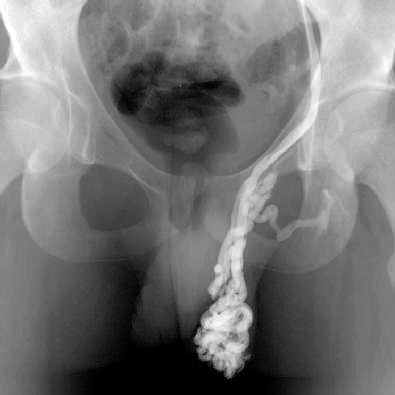

Венография Рентгенологическое исследование вен семенного канатика после введения контрастного вещества. (Редко используется) Наблюдение, склеротерапия, эмболизация, хирургическое вмешательство (варикоцелектомия)

При ультразвуковом исследовании у мужчин с варикоцеле обычно обнаруживаются специфические изменения в венах семенного канатика — это могут быть анэхогенные извитые или узловатые участки. При этом диаметр вен зачастую превышает норму на три миллиметра и более.

Ультразвуковое исследование играет ключевую роль не только в точной диагностике варикозного расширения вен, но и на этапе подготовки к операции, так как варикоцеле требует хирургического вмешательства для лечения.

Аппаратная диагностика предоставляет врачу детальную информацию о состоянии тканей и уровне кровотока в них.

Диагностика варикоселе